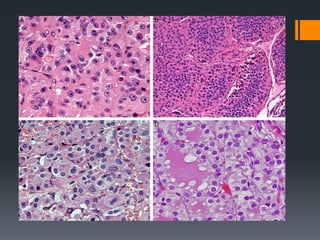

Nuclear Enlargement

The nuclear/cytoplasmic ratio is increased.

Nuclear overlapping, nuclear crowding, and loss of

the basal polarization of nuclei.

The last feature is particularly important when

dealing with benign follicular lesions that exhibit

papillary architecture.

Nuclear Membrane Irregularities

Hallmark of PTC - loss of nuclear roundness. Oval or

elongated nuclei are one form of irregularity.

A “raisinoid” or “cerebriform” appearance, because of

indentations, or “angulated” nuclear membrane

irregularities, are important features of PTC.

The more nuclear membranes fold into themselves, the

more florid nuclear features such as “grooves” or

“intranuclear pseudoinclusions” .

The most florid feature, the intranuclear cytoplasmic

pseudoinclusion, results from deep invaginations of the

cytoplasm. (Not required)

Peripheral Chromatin Margination

 Hypo chromatic nuclei because of peripheral margination of

chromatin and clearing of nucleoplasm

 Chromatin margination results in the optically clear or

ground-glass appearance of the nuclei.

Prominent Micronucleoli

 Multiple small eccentric micronucleoli that are distinct from

the single, usually central nucleolus of nontumorous thyroid

follicular epithelial cells